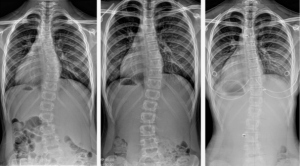

В заключение приведем пример работы КП2 по сравнению с эталонными измерениями и измерениями ВРБО (рис. 3).

Измерения ВРБО существенно отличались от эталона — от 4 до 12°. Программа правильно определила и оценила все имеющиеся дуги деформации, разница между эталонным и автоматическим измерением угла Cobb составила 1—2° и определена как несущественная.

Демонстрация работы компьютерной программы после дообучения (КП2): а, г — эталонные ручные измерения; б, д — измерения врача-рентгенолога без опыта в вертебрологии; в, е — автоматические измерения КП2